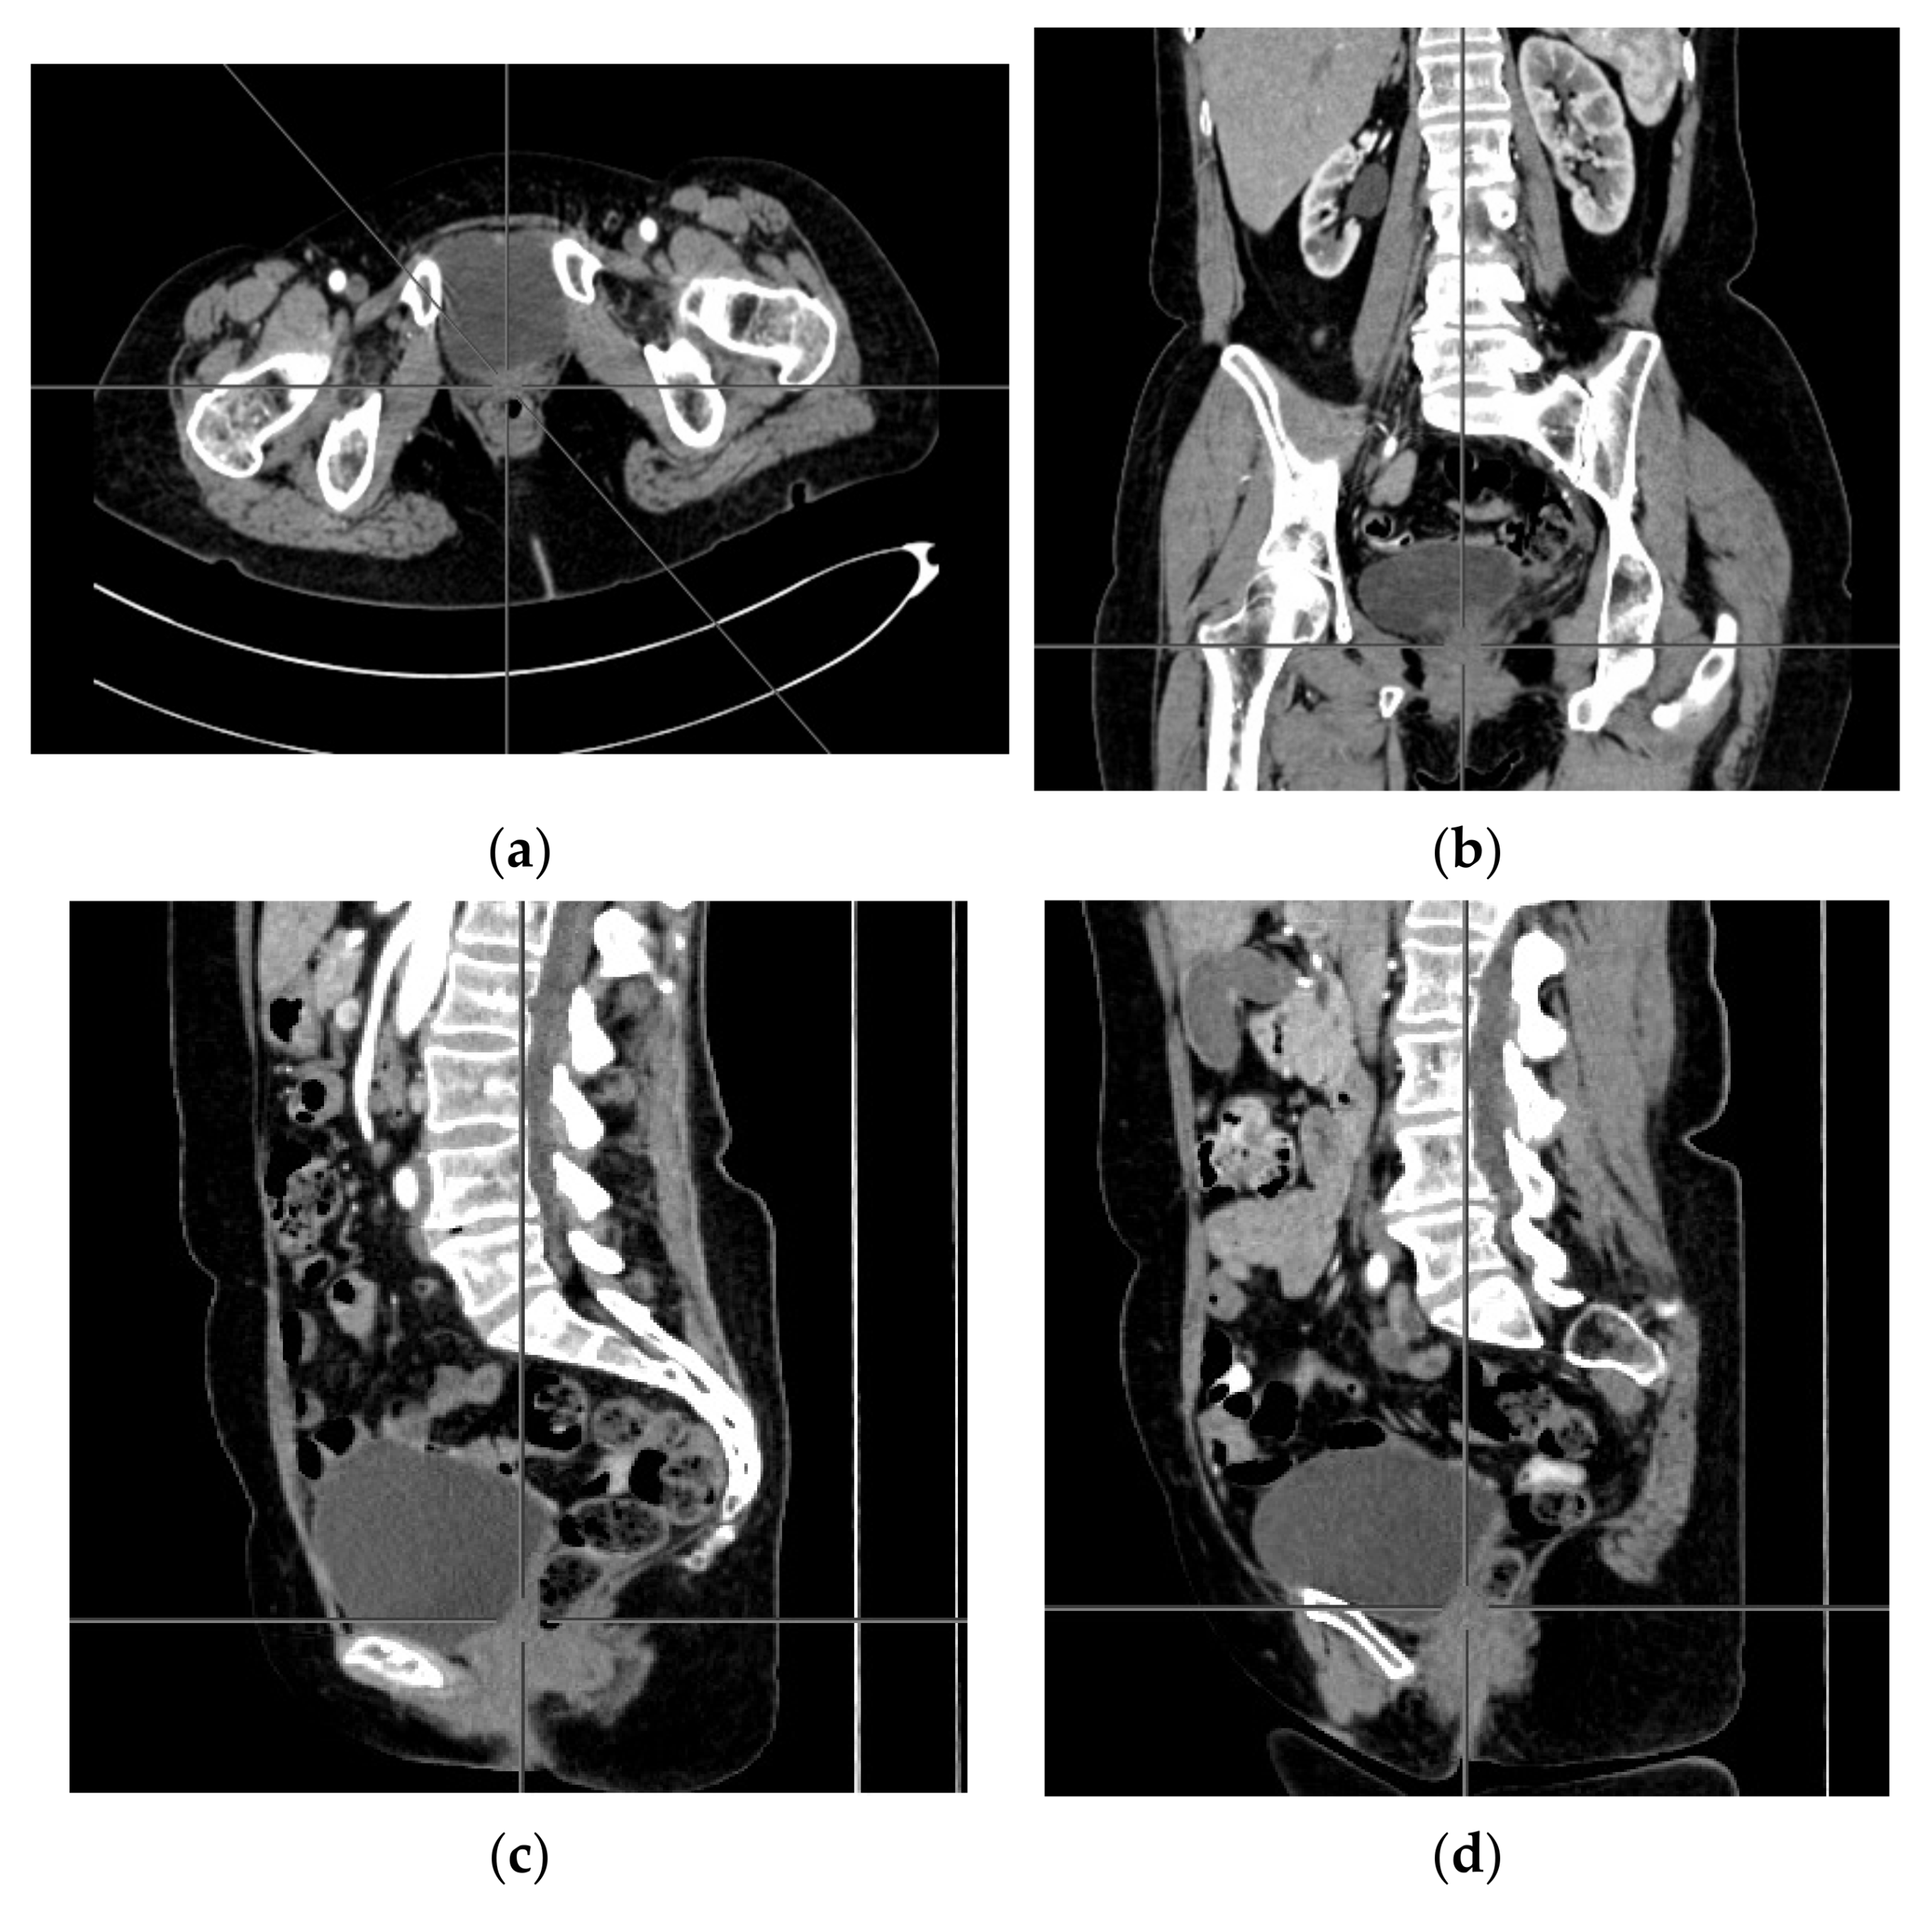

2. Case Report